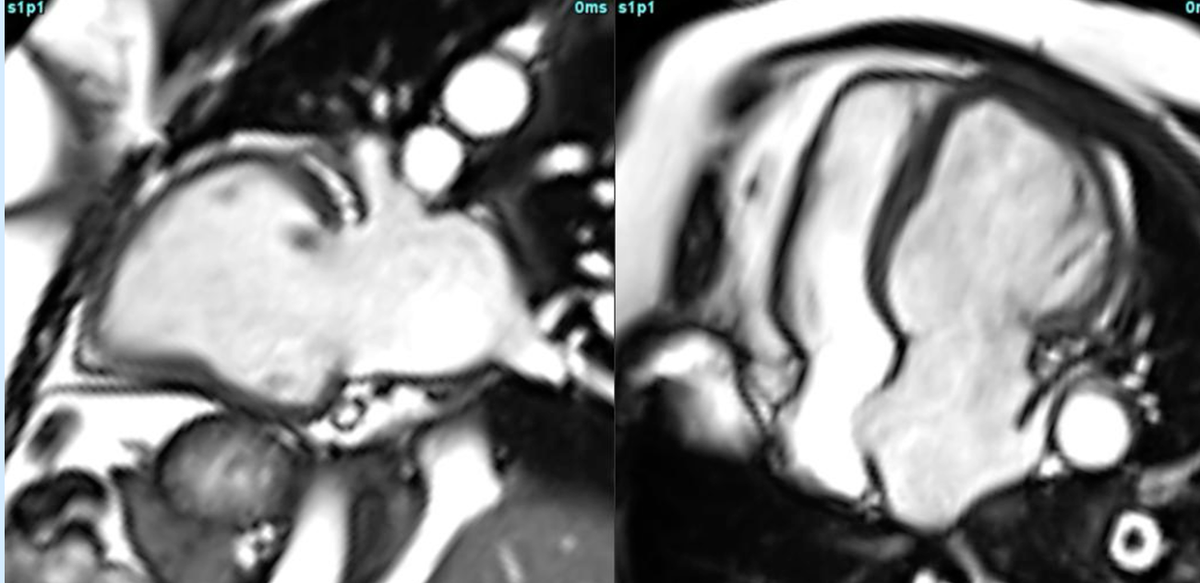

Valvular HD

Multifaceted role of CMR